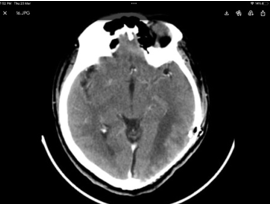

Patient underwent left parieto occipital craniotomy and gross total excision of the lesion ([Figure 2]) Histopathology reported as primary Non-Hodgkin’s lymphoma favoring diffuse large B cell lymphoma. ([Figure 3]). PET CT was done showed post-operative changes without any obvious metabolically active lesion in the brain parenchyma. Case was discussed in tumor board and has been planned for 4 cycles of chemotherapy with R-MPV (Rituximab, Methotrexate, Procarbazine and Vincristine) and then reassess.